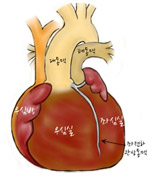

[그림2] 완전대혈관전위증 심장

대동맥이 폐동맥 앞으로 위치 하며 우심실과연결되어 있고 폐동맥은 좌심실과 연결되어있음